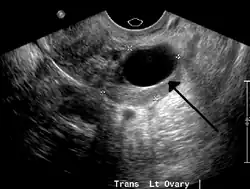

Transvaginal ultrasonography of a hemorrhagic ovarian cyst, probably originating from a corpus luteum cyst. The coagulating blood gives the content a cobweb-like appearance. -

Ovarian cysts are usually diagnosed by pelvic ultrasound, CT scan, or MRI, and correlated with clinical presentation and endocrinologic tests as appropriate.[15] Ultrasound is the most important imaging modality, as abnormalities seen in a CT scan sometimes prove to be normal in ultrasound.[5][8] If a different modality is needed, then MRIs are more reliable than CT scans.[5]

Ultrasound

Usually, an experienced sonographer can readily identify benign ovarian cysts, often with a level of accuracy that rivals other approaches.[5]

Follow-up imaging in women of reproductive age for incidentally discovered simple cysts on ultrasound is not needed until 5 cm, as these are usually normal ovarian follicles. Simple cysts 5 to 7 cm in premenopausal females should be followed yearly. Simple cysts larger than 7 cm require further imaging with MRI or surgical assessment. Because they are large, they cannot be reliably assessed by ultrasound alone; it can be difficult to see posterior wall soft tissue nodularity or thickened septation due to limited ultrasound beam penetrance at this size and depth. For the corpus luteum, a dominant ovulating follicle that typically appears as a cyst with circumferentially thickened walls and crenulated inner margins, follow up is not needed if the cyst is less than 3 cm in diameter.[8] In postmenopausal women, any simple cyst greater than 1 cm but less than 7 cm needs yearly follow-up, while those greater than 7 cm need MRI or surgical evaluation, similar to reproductive age females.[16]